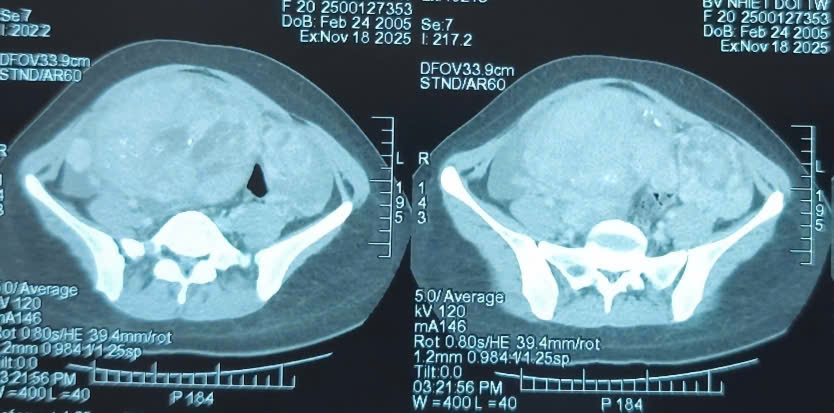

Hình ảnh chụp cắt lớp cho thấy khối u chiếm gần toàn bộ bụng dưới của nữ bệnh nhân.

Khám lâm sàng ghi nhận một khối bất thường lớn tại vùng hạ vị. Kết quả chụp cắt lớp vi tính cho thấy khối u kích thước 110 x 163 x 244mm, bờ không đều, bên trong có nốt vôi hóa và xuất hiện dịch tự do trong ổ bụng. Bệnh nhân được chỉ định phẫu thuật cắt bỏ toàn bộ khối u.